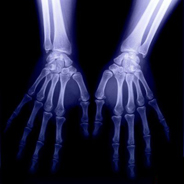

В медицинской практике рентгеновские лучи начали широко применяться лишь с 20-х годов XX века. Рентгеновское излучение применяется с целью распознания (диагностики) многих повреждений и заболеваний человека, как на ранних, так и на поздних стадиях. Различные ткани человеческого тела по-разному поглощают рентгеновские лучи. Костные ткани плотнее (они состоят на 70% из минеральных солей, 20% органических веществ и 10% воды), поэтому они лучше, чем мягкие ткани (кожа, мышцы, сосуды, жировая клетчатка), поглощают лучи. На фотоснимке кости хорошо видны, им будет соответствовать светлое место. Мягкие ткани, наоборот, беспрепятственно пропускают лучи, поглощая их лишь частично. Мягкие ткани оставляют на снимке темные пятна.

Чем меньше будет расстояние, которое должны преодолеть рентгеновские лучи, тем ярче будет снимок. Поэтому кассета с рентгеновской пленкой и рентгеновская трубка располагаются как можно ближе к исследуемой части тела. Такое рентгенологическое исследование называется контактной рентгенограммой; изображение костей практически в натуральную величину. Кроме того, снимок получается достаточно четким. В зависимости от того, рентгенограмму какой части тела необходимо сделать, меняется положение тела пациента. Например, при рентгенологическом исследовании костей кисти пациент находится в сидячем положении. Он кладет свою ладонь на кассету, в которой находится пленка. Если проводится исследование ребер или позвоночника, то пациента укладывают на стол, а кассета подкладывается под спину. Обычно выполняют два рентгеновских снимка одной и той же кости: в положении спереди и сбоку.

Очевидные изменения (например, переломы костей или вывихи) на рентгенограмме заметит даже не профессионал. Для врача же рентгенограммы содержат гораздо больше информации. Он может обнаружить и опухоль кости, и находящееся в кости инородное тело, особенно металлическое. Кроме того, рентгенограмма дает представление о плотности кости, а на основе этого врач тоже может диагностировать некоторые болезни.

На рентгенограммах костей можно увидеть так называемые эпифизарные хрящи (пластинки роста), которые с возрастом замещаются костной тканью, и определить, растет ли еще человек. Приблизительно возраст можно определить и по костям запястья.